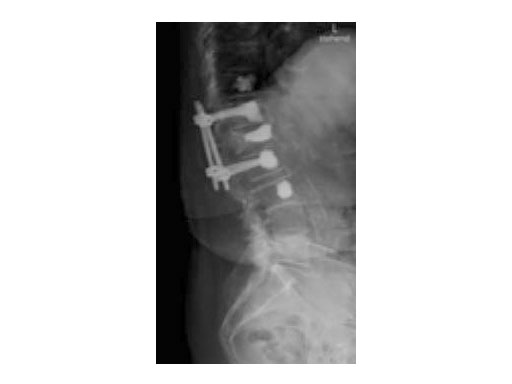

Synflate can be used stand-alone or in combination with posterior instrumentation (see the clinical cases within this article).

A 78-year-old woman was affected by steroid induced osteoporosis. She had persisting pain (mechanic and muscular) due to static imbalance (hyperkyphosis) and nonunion 8 months after a minor trauma with a vertebral compression fracture and vertebra plana of L1, and development of symptomatic stenosis of the spinal canal with loss of mobility over time. Pre-existing degenerative lumbar scoliosis was increased by the fracture.